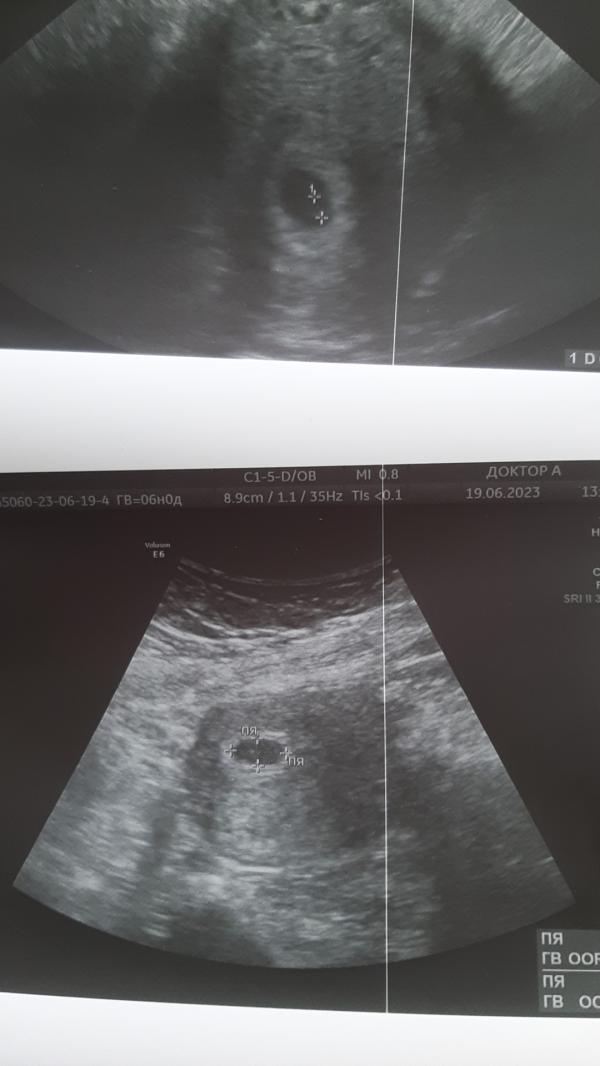

Вести с полей 🙂 пока картина такая, по узи нашли плодное яйцо и желточный мешочек, сказали эмбриончик еще не появился,но обязательно будет, так что ждем дальше. 🤞🙏